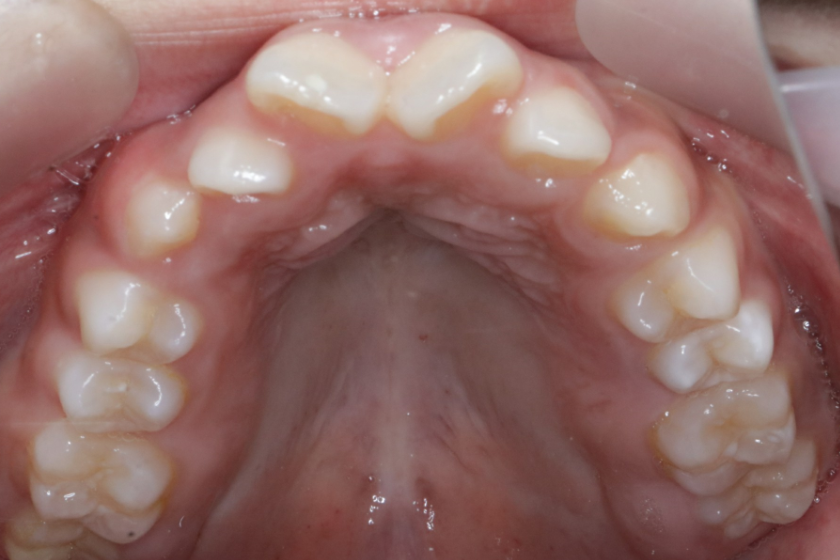

治疗前                        治疗后

儿童错合畸形早期矫治是阻断影响儿童颌骨、牙齿正常发育的因素,促进颌面部正常发育,降低II期矫正的难度,减少II期矫正的时间,甚至不需要II期矫正。让孩子早期获得自信,绽放灿烂笑容。

术前→术后